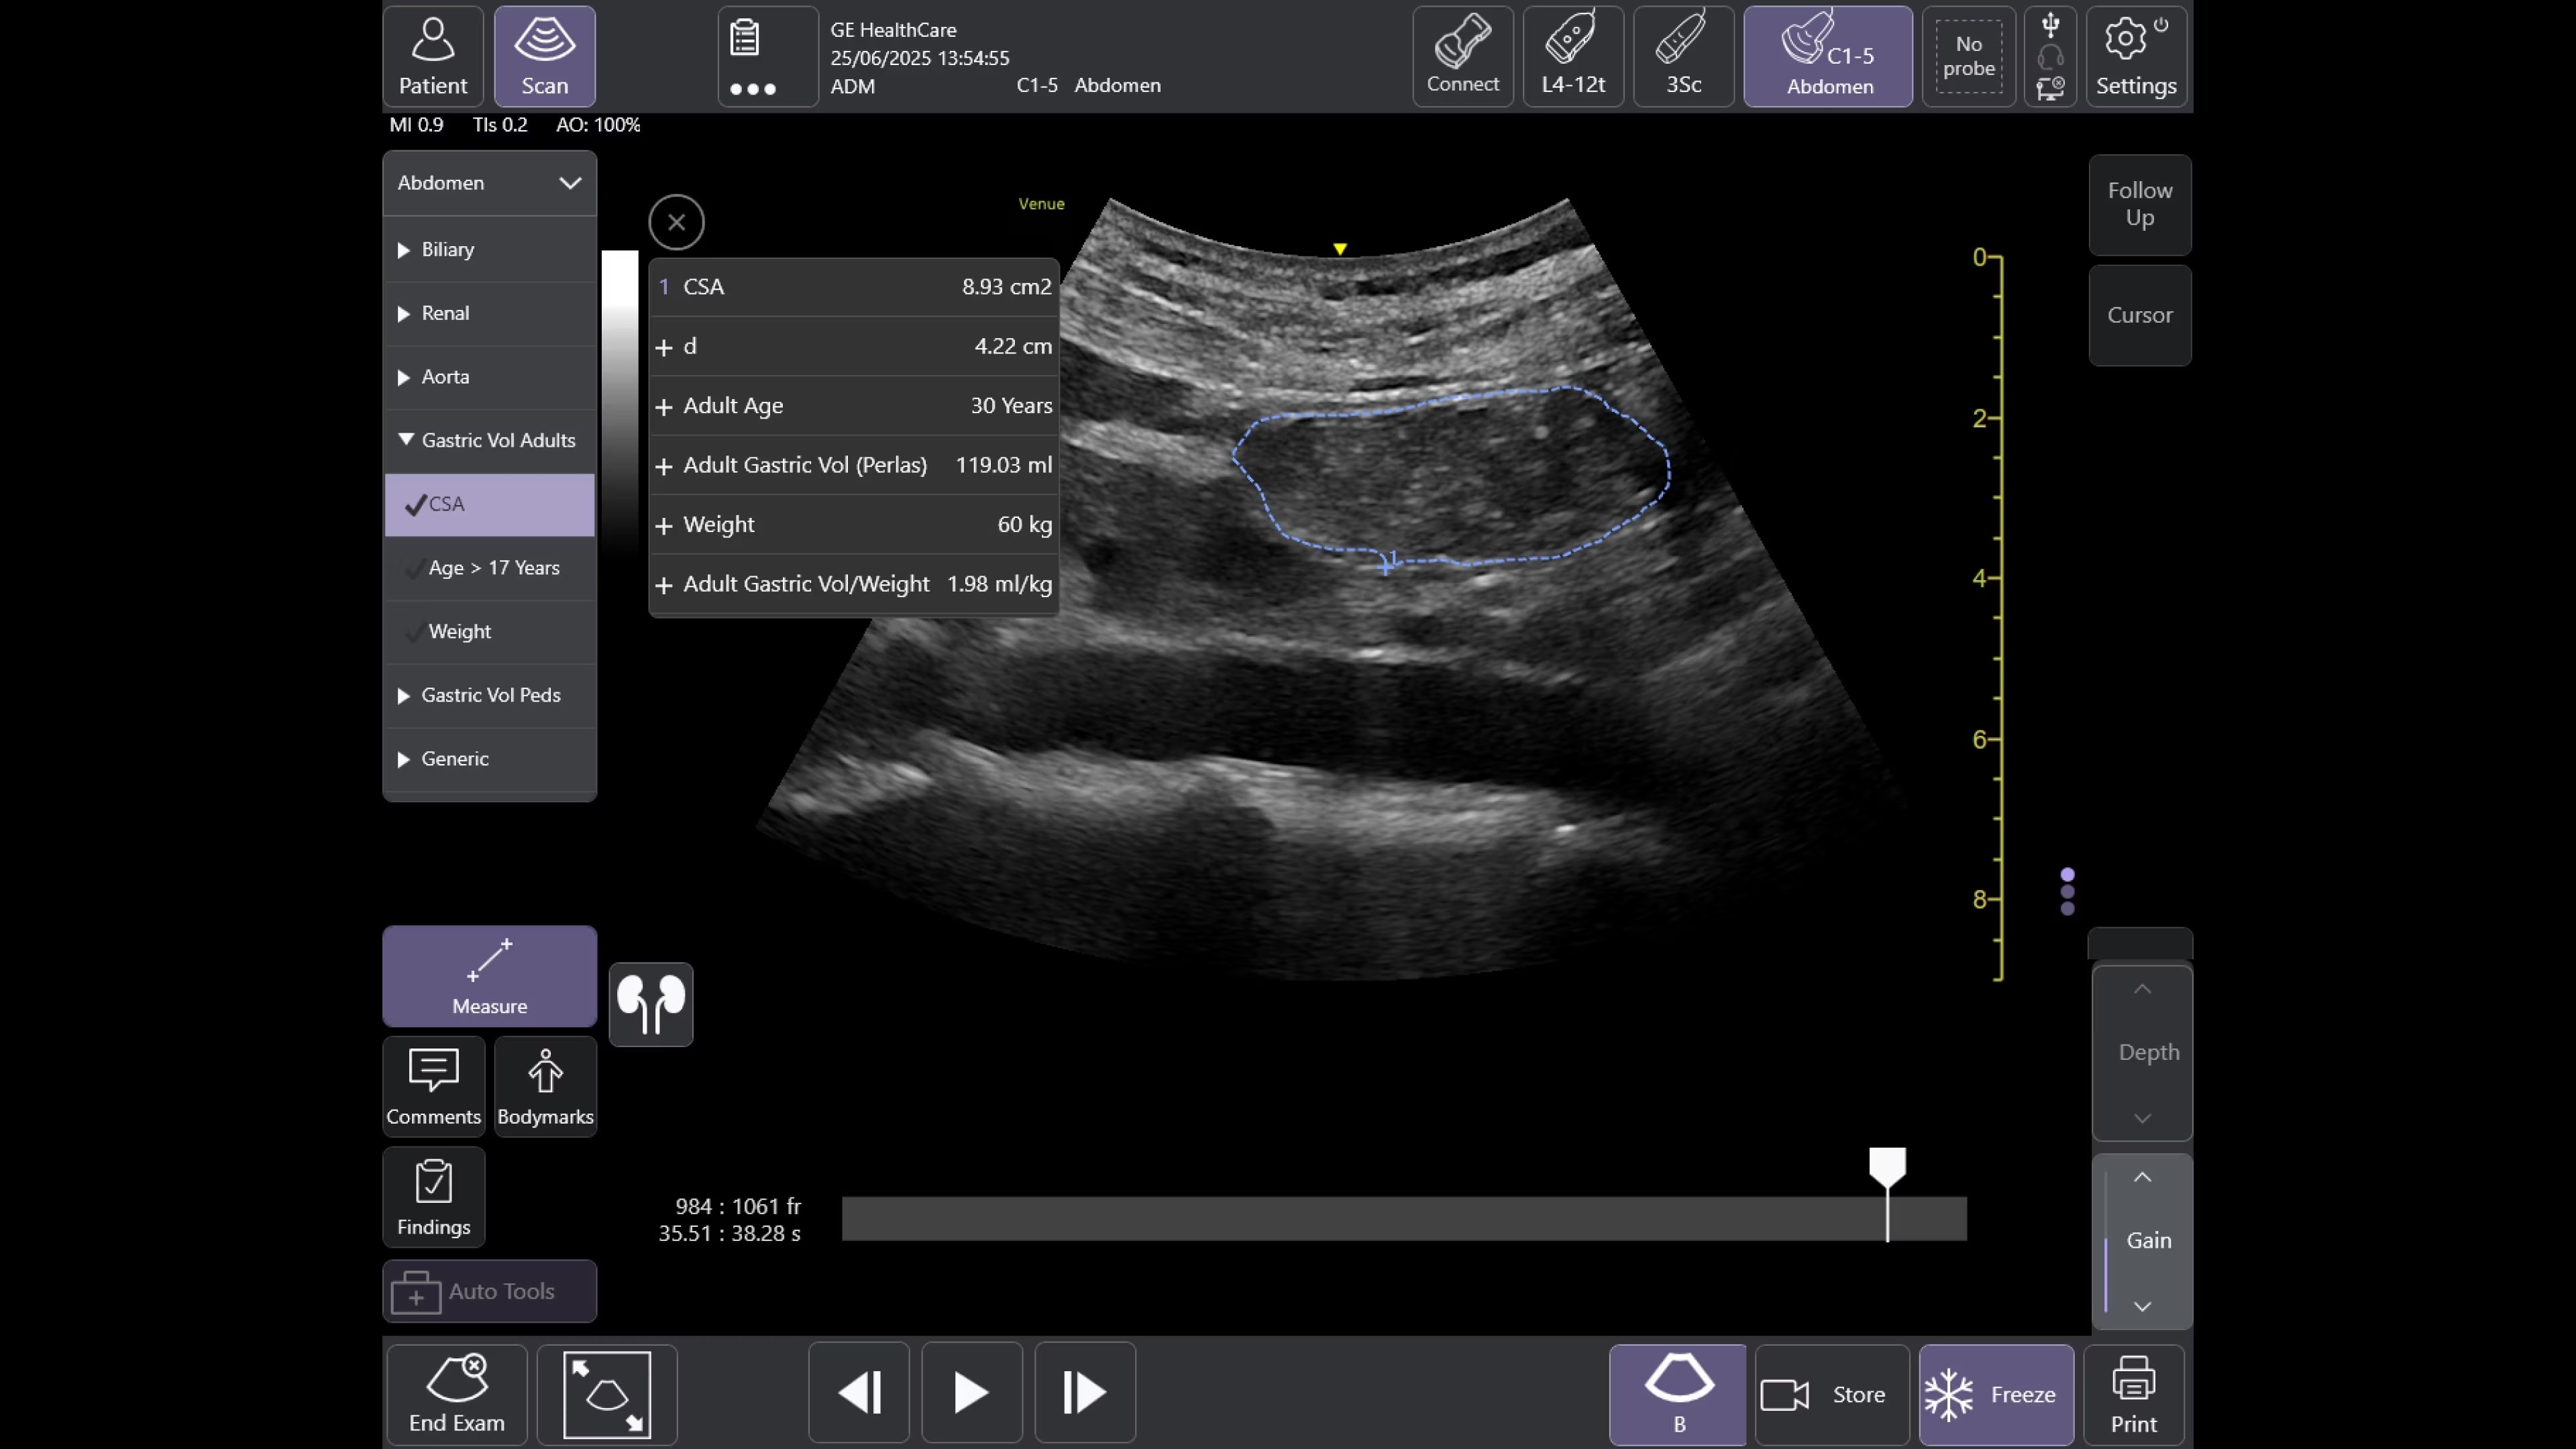

Offering a simple, fast, and precise way to enhance your clinical decision making in a variety of perioperative situations, such as assessment of endotracheal tube placement, cardiac function, pulmonary function, and aspiration risk.

Ready for sudden changes in patient health

From its straightforward design to its AI-enabled Auto Tools, the Venue Family of point of care ultrasound systems empower physicians to make fast assessments in tough situations.